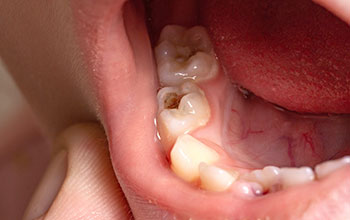

• Periodontal Disease専門医による 重度歯周病治療、 歯周組織再生療法で 歯を残します